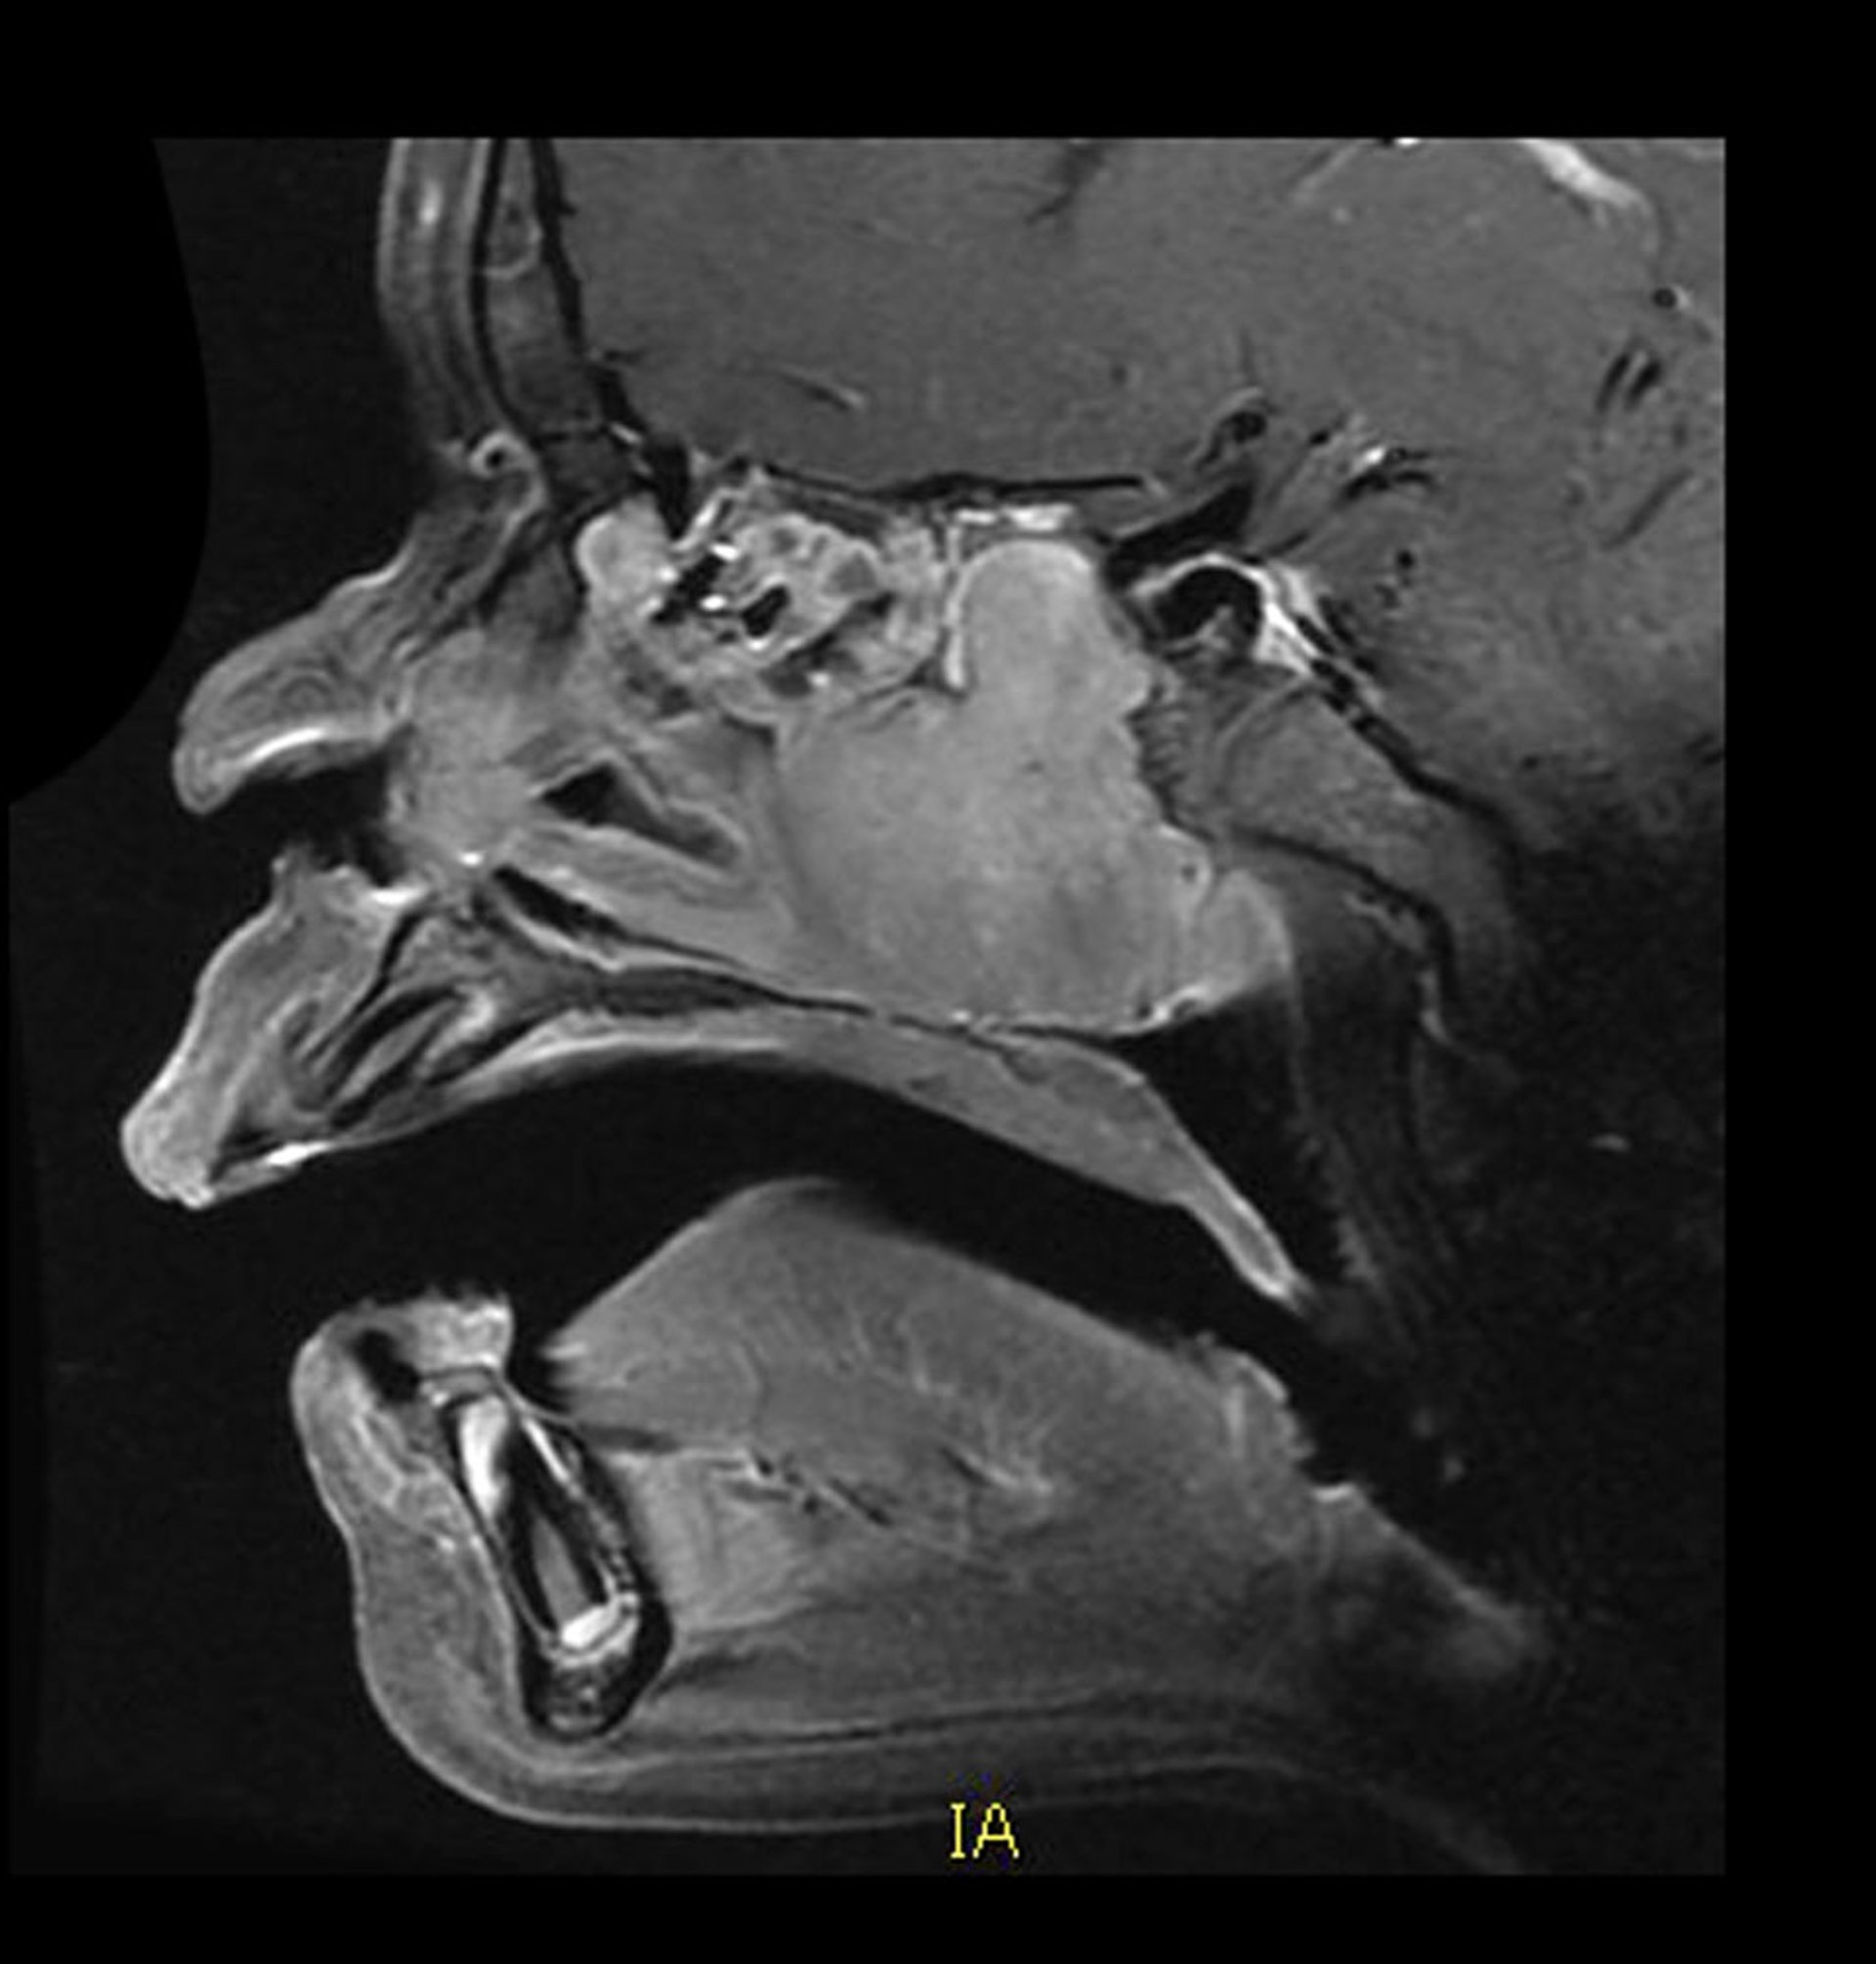

Juvenile Nasopharyngeal Angiofibroma (MRI)

This sagittal, contrast-enhanced MRI shows the typical location and appearance of a vascular juvenile nasopharyngeal angiofibroma. There is a homogeneously enhancing mass in the posterior nasal cavity growing posteriorly into the sphenoid sinus. There is associated bone destruction also.